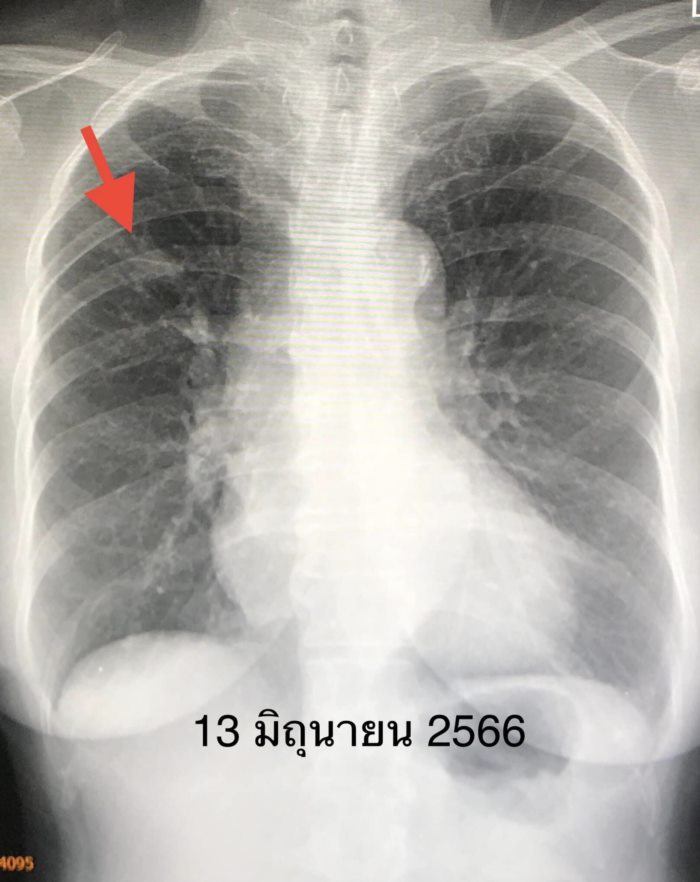

แพทย์จึงให้คนไข้เข้าโครงการช่วยเหลือให้เข้าถึงยารักษาโรคมะเร็งตัวใหม่ Mobocertinib (Exkivity) ที่โรงพยาบาลรามาธิบดี ให้ขนาด 40 มิลลิกรัม กิน 4 เม็ดวันละครั้งทุกวัน เริ่มเดือนเมษายน 2566 ระยะแรกมีผลข้างเคียงเล็กน้อย มีผื่นและแผลในปาก หลังปรับยาเหลือ 3 เม็ดวันละครั้ง ผลข้างเคียงลดลง เดือน มิถุนายน 2566 หลังกินยา 2 เดือน ผู้ป่วยตอบสนองต่อยาตัวใหม่นี้ดีมาก เอกซเรย์พบก้อนในปอดขนาดเล็กลงมาก ต้องติดตามต่อไปว่า ยาตัวใหม่นี้จะใช้ได้ผลนานแค่ไหน